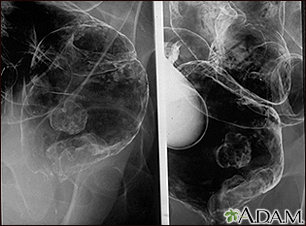

Rectal cancer - x-rayBackRectal cancer - x-rayA barium enema in a patient with cancer of the rectum. E-mail FormEmail ResultsName:Email address:Recipients Name:Recipients address:Message: